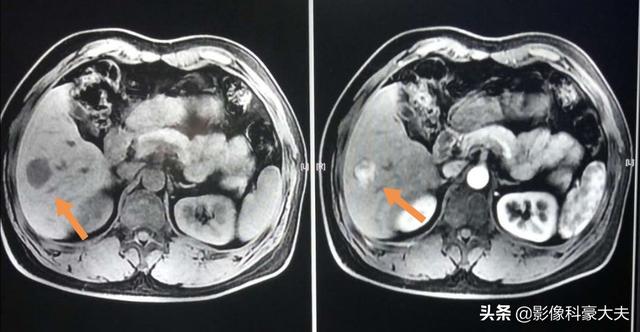

Bei diesem Mann mittleren Alters mit einer Vorgeschichte von chronischer Hepatitis B wurde im Ultraschall eine ungleichmäßige Hypoechoizität im unteren Segment des rechten Leberlappens festgestellt, mit erhöhtem Alpha-Fetoprotein in den Labortests, und eine weitere Magnetresonanztomographie ergab einen klassisch abgerundeten Bereich mit niedrigem Signal und ungleichmäßigem Enhancement beim Enhancement-Scanning, wodurch klar wurde, dass es sich um ein kleines hepatozelluläres Karzinom handelte, das seit fast drei Jahren operiert worden war.

Bei typischen Läsionen kann auch ein erweitertes CT die Diagnose bestätigen. Einige kleine Leberkarzinome sind heikel und sehen atypisch aus und erfordern möglicherweise ein erweitertes MRT-Scanning mit speziellen Kontrastmitteln, das etwas teurer ist und eine vorherige Terminvereinbarung erfordert.